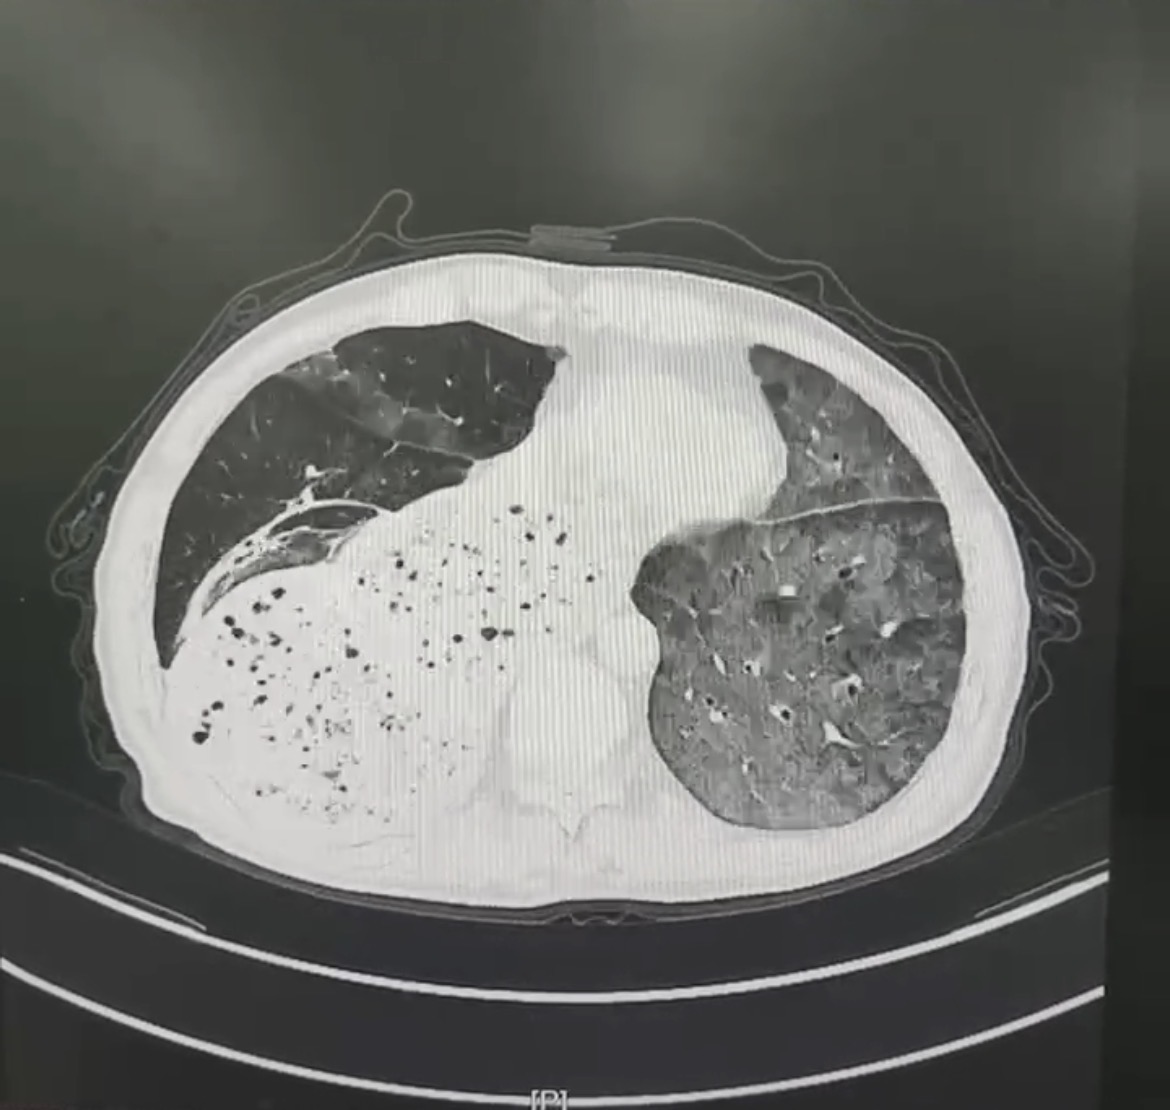

患者赵先生,反复的胸闷、呼吸困难一年有余,每一次呼吸都成为一种负担。随着时间推移,病情逐渐恶化,平静休息时难以缓解,活动后症状加剧。赵先生曾辗转多家医院就诊,然而疾病始终诊断不明,治疗效果不佳,病情时有反复,令患者和家属备受煎熬。近期,患者的病情急转直下,胸闷气急加重,甚至出现呼吸衰竭。门诊胸部CT提示两肺弥漫性渗出病变,紧急收入我院。

胸部CT

入院后,医生迅速展开全面细致的检查,支气管镜检查发现患者肺泡灌洗液成米汤样,并具有明显分层现象,结合后续肺泡灌洗液报告,中性粒细胞占比高达99.0%,并可见吞噬细胞,镜下可见大量脂肪空泡,苏丹 III 染色呈阳性,这些证据指向疾病的最终真相——脂质性肺炎。